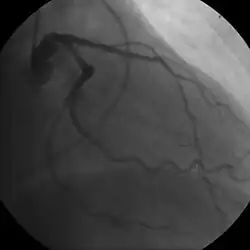

For stable symptomatic patients, several non-invasive tests can diagnose CAD depending on pre-assessment of the risk profile. Noninvasive imaging options include; Computed tomography angiography (CTA) (anatomical imaging, best test in patients with low-risk profile to "rule out" the disease), positron emission tomography (PET), single-photon emission computed tomography (SPECT)/nuclear stress test/myocardial scintigraphy and stress echocardiography (the three latter can be summarized as functional noninvasive methods and are typically better to "rule in"). Exercise ECG or stress test is inferior to non-invasive imaging methods due to the risk of false-negative and false-positive test results. The use of non-invasive imaging is not recommended on individuals who are exhibiting no symptoms and are otherwise at low risk for developing coronary disease.[75][76] Invasive testing with coronary angiography (ICA) can be used when non-invasive testing is inconclusive or show a high event risk.[74]

Stable angina is the most common manifestation of ischemic heart disease, and is associated with reduced quality of life and increased mortality. It is caused by epicardial coronary stenosis, which results in reduced blood flow and oxygen supply to the myocardium.[78] Stable angina is short-term chest pain during physical exertion caused by an imbalance between myocardial oxygen supply and metabolic oxygen demand. Various forms of cardiac stress tests may be used to induce both symptoms and detect changes by way of electrocardiography (using an ECG), echocardiography (using ultrasound of the heart) or scintigraphy (using uptake of radionuclide by the heart muscle). If part of the heart seems to receive an insufficient blood supply, coronary angiography may be used to identify stenosis of the coronary arteries and suitability for angioplasty or bypass surgery.[79]